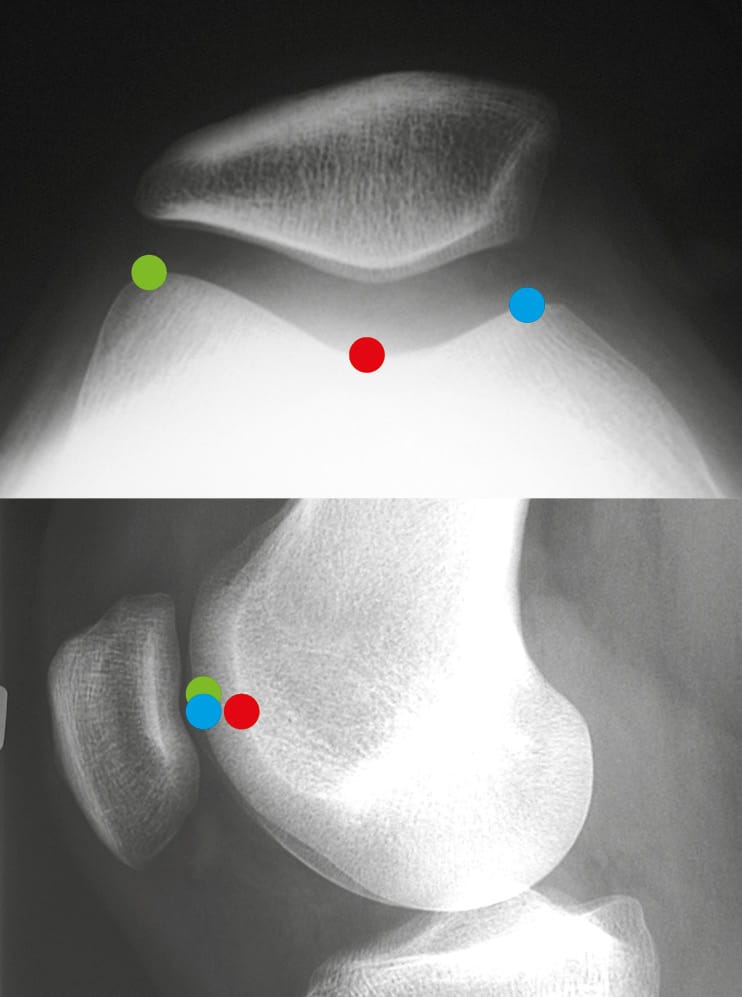

On this diagram of the lateral knee (Figure 15), one can recognise the trochlear groove line A, but also the two condyles, lateral B and medial C. This trochlear groove line A remains distant from the lines of the two condyles B and C. In fact, on the axial view, these three lines are found with the medial and lateral facets of the trochlea, as well as the trochlear groove line.

The axial view (Figure 16) is conventionally performed at 30° of flexion. It does not account for the proximal part of the trochlea. The lateral X-ray allows for the analysis of the trochlea from its most proximal part down to the notch.

This is the true value of the lateral view: The analysis of the proximal portion, the upper part of the trochlea.

On this lateral radiograph (Figure 16), one can recognise the trochlear groove line but also the two condyles, lateral and medial. This trochlear groove line remains distant from the lines of the two condyles. In fact, these three lines are found on the axial view, with the medial and lateral facets of the trochlea as well as the trochlear groove line. The trochlear groove line always remains distant from the line of the two condyles, even in its proximal part.

Here is a very clear crossing sign (Figure 17) on the lateral radiograph. From this point upwards, the trochlea is flat or even convex. As the crossing occurs quite low on the trochlea, it is very dysplastic, and this can be diagnosed on the axial view at 30° of flexion.

The third factor retained in 1987 was patellar tilt.

Patellar tilt is the expression of malalignment of the patella in the horizontal plane. Patellar tilt depends on bone anatomy but also on the retinacula or patellar ligaments and the quadriceps muscle.

The presence of patellar tilt greater than 20° with relaxed quadriceps was found in 83% of patients belonging to the objective patellar instability group. This tilt was initially attributed to VMO dysplasia. Our subsequent work showed that trochlear dysplasia, patellar height, and the TT-TG value evidently influenced patellar tilt.

On a trochlear section passing through the Roman arch, the patellar tilt, which is the angle formed by a line passing through the long axis of the patella and the tangent to the posterior condyles, is, here, 28° with relaxed quadriceps (Figure 30).

The patellar tilt is 35° with contracted quadriceps. When the patella is high, it is sometimes necessary to superimpose the trochlear and patellar sections (Figure 31).